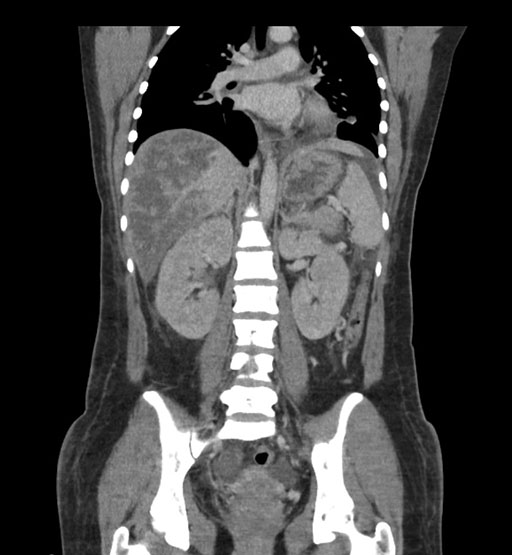

Coronal Venous

Imaging analysis

Based on initial findings, which issue(s) would you be most concerned about?